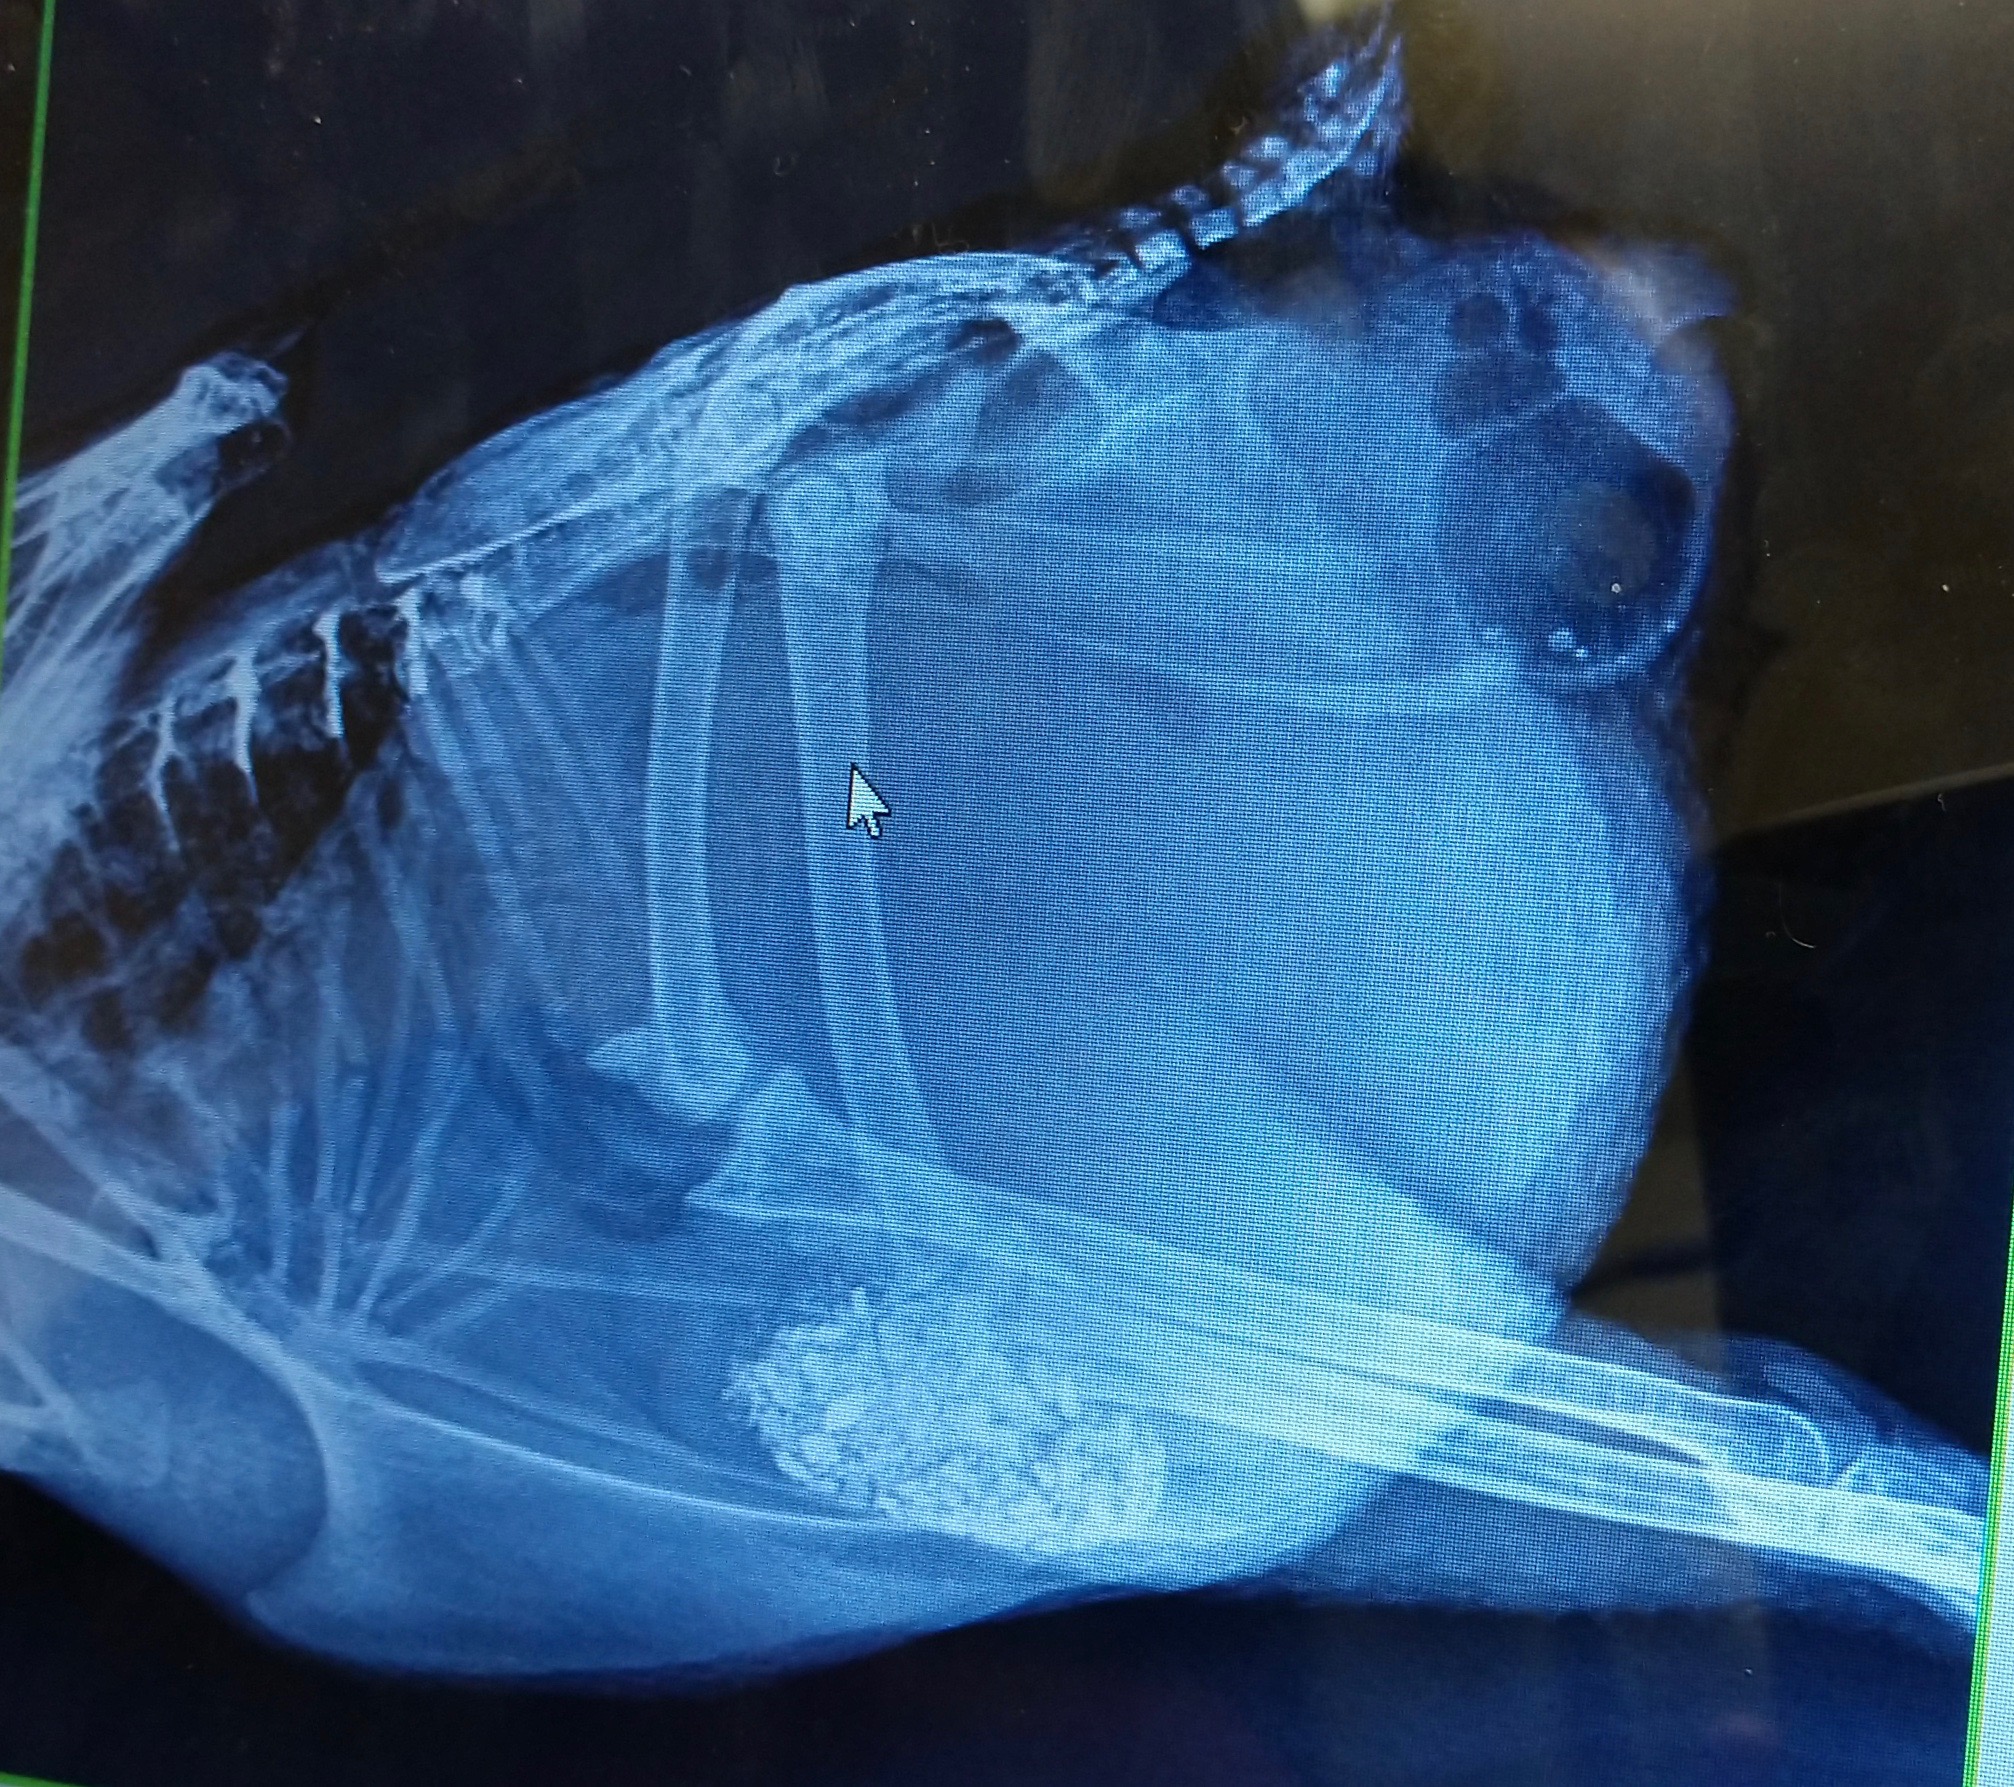

You’ll note that in some of the x-rays you can see a mass that looks like a ball of crumpled aluminum foil in her oviduct region. Those images are from the first visit, the ones with it missing are after she passed that obstruction. The mass itself is what’s in the Ziploc bag, both intact and after the vet broke it apart to examine contents. I wish we could have gotten a cross-section image, but at the time I felt it might be important for the vet to see exactly how it came out and cross reference to confirm nothing appeared to have been left behind.

Can you spot something important that our vet overlooked? We still haven’t been able to get a very clear picture of what’s going on apart from that blockage, but suspect something is, just based on the continuing digestive issues and apparent fluid still present at the second x-ray. I feel like she’s laying internally periodically and reabsorbing fluid between. Outwardly, she is acting like her system is on and functioning, but nothing comes of her efforts, so that has me concerned that she is doing something and it’s just not making it’s way out. I imagine septic EYP can be ruled out, as I don’t think we would be seeing these rebounds of full energy/appetite if anything had gone septic. She has good and bad days, and the bad ones always go hand-in-hand with the watery poop. She’s definitely got us scratching our heads.

Dr Bowes: The vet did a great job of the x-rays. They indicate the ureters are full of crates, a sign of dehydration, the intestines look normal, there is a lot of internal fat. The mass is a collection of debris from the oviduct. It is crumbly and friable, the result of a hemorrhagic component. The intestines appear to be bunched up. There is something obstructing the full view of the abdomen. Is that fat or yolk peritonitis?